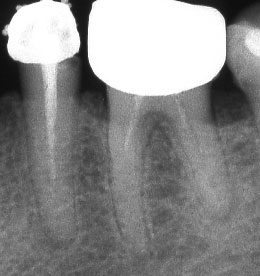

При наличие на огнище на възпаление около корените на зъба добре проведеното лечение води до изчезване на изменението. На снимката долу едва една седмица след пролекуване на каналите се наблюдава известна редукция на патологичния процес. За период от 6 месеца до 2 години е възможно да се наблюдава пълен оздравителен процес.

Винаги е необходимо лекуващият да се стреми към този резултат: